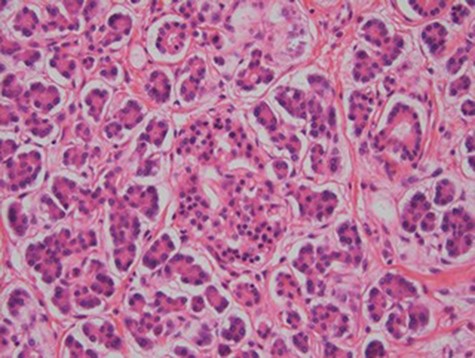

At laparoscopy, there were very dilated and inflamed loops of small bowel, and the appendix appeared normal macroscopically. Due to the extent of bowel dilatation obscuring adequate laparoscopic vision and assessment, decision was made to convert to an open procedure. At laparotomy, there was a nodular mass in the jejunal mesentery measuring about 3 cm in diameter with central necrotic tissue (Fig. 1). As it was adherent to the surrounding bowel, a limited small bowel resection was performed (Fig. 2) with side to side stapled anastomosis. Histology revealed normal small bowel wall with a mesenteric nodular mass comprised of architecturally normal pancreatic tissue including exocrine ducts and endocrine islets of Langerhans (Figs 3–5), consistent with a diagnosis of mesenteric heterotopic pancreas. His post-surgical recovery was uneventful and was discharged after five days of stay in hospital. He had an outpatient magnetic resonance imaging (MRI) of the pancreas which reviewed normal pancreas tissue, and he was followed up three months post-surgery.

Necrosis (star) and acute inflammation with the presence of stromal neutrophils (arrow) within the mesenteric mass (H&E stain, x100).